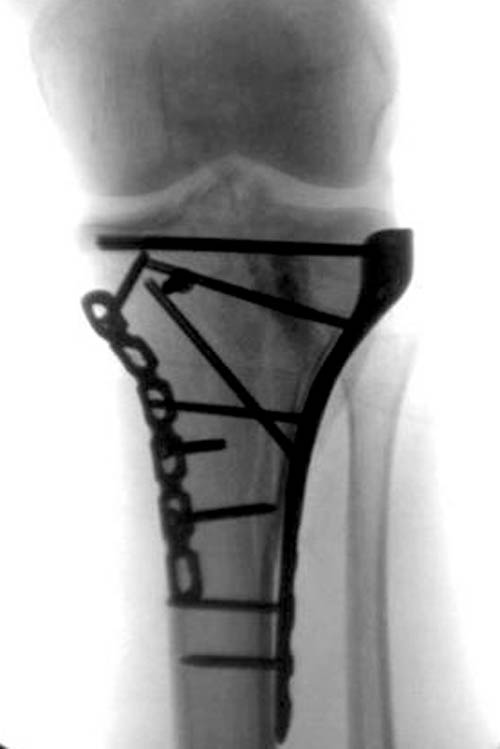

На боковом рентгене, явный задний смещенный компонент. КТ поможет

увидеть "вершину" перелома, куда надо поставить антискользящую пластину

из заднего или задне-медиальнего доступа. Для стабилизации боковой

колонны традиционный боковой доступ через Girdle tubercle с длинной

блокирующей пластиной. Одна задняя подпорка не удержит медиальную

колонну, требуется длинная медиальная пластина.

Пластин для медиальной колонны не бывает, и поэтому подойдет любая

тонкая пластина. Сегодня отходим от установки для тибиал плато толстых

пластин, больше, чем 3.5 мм. Задача удержать, а нагрузка разрешается

только после сращения в 3 мес., и поэтому нет смысла устанавливать

толстые пластины